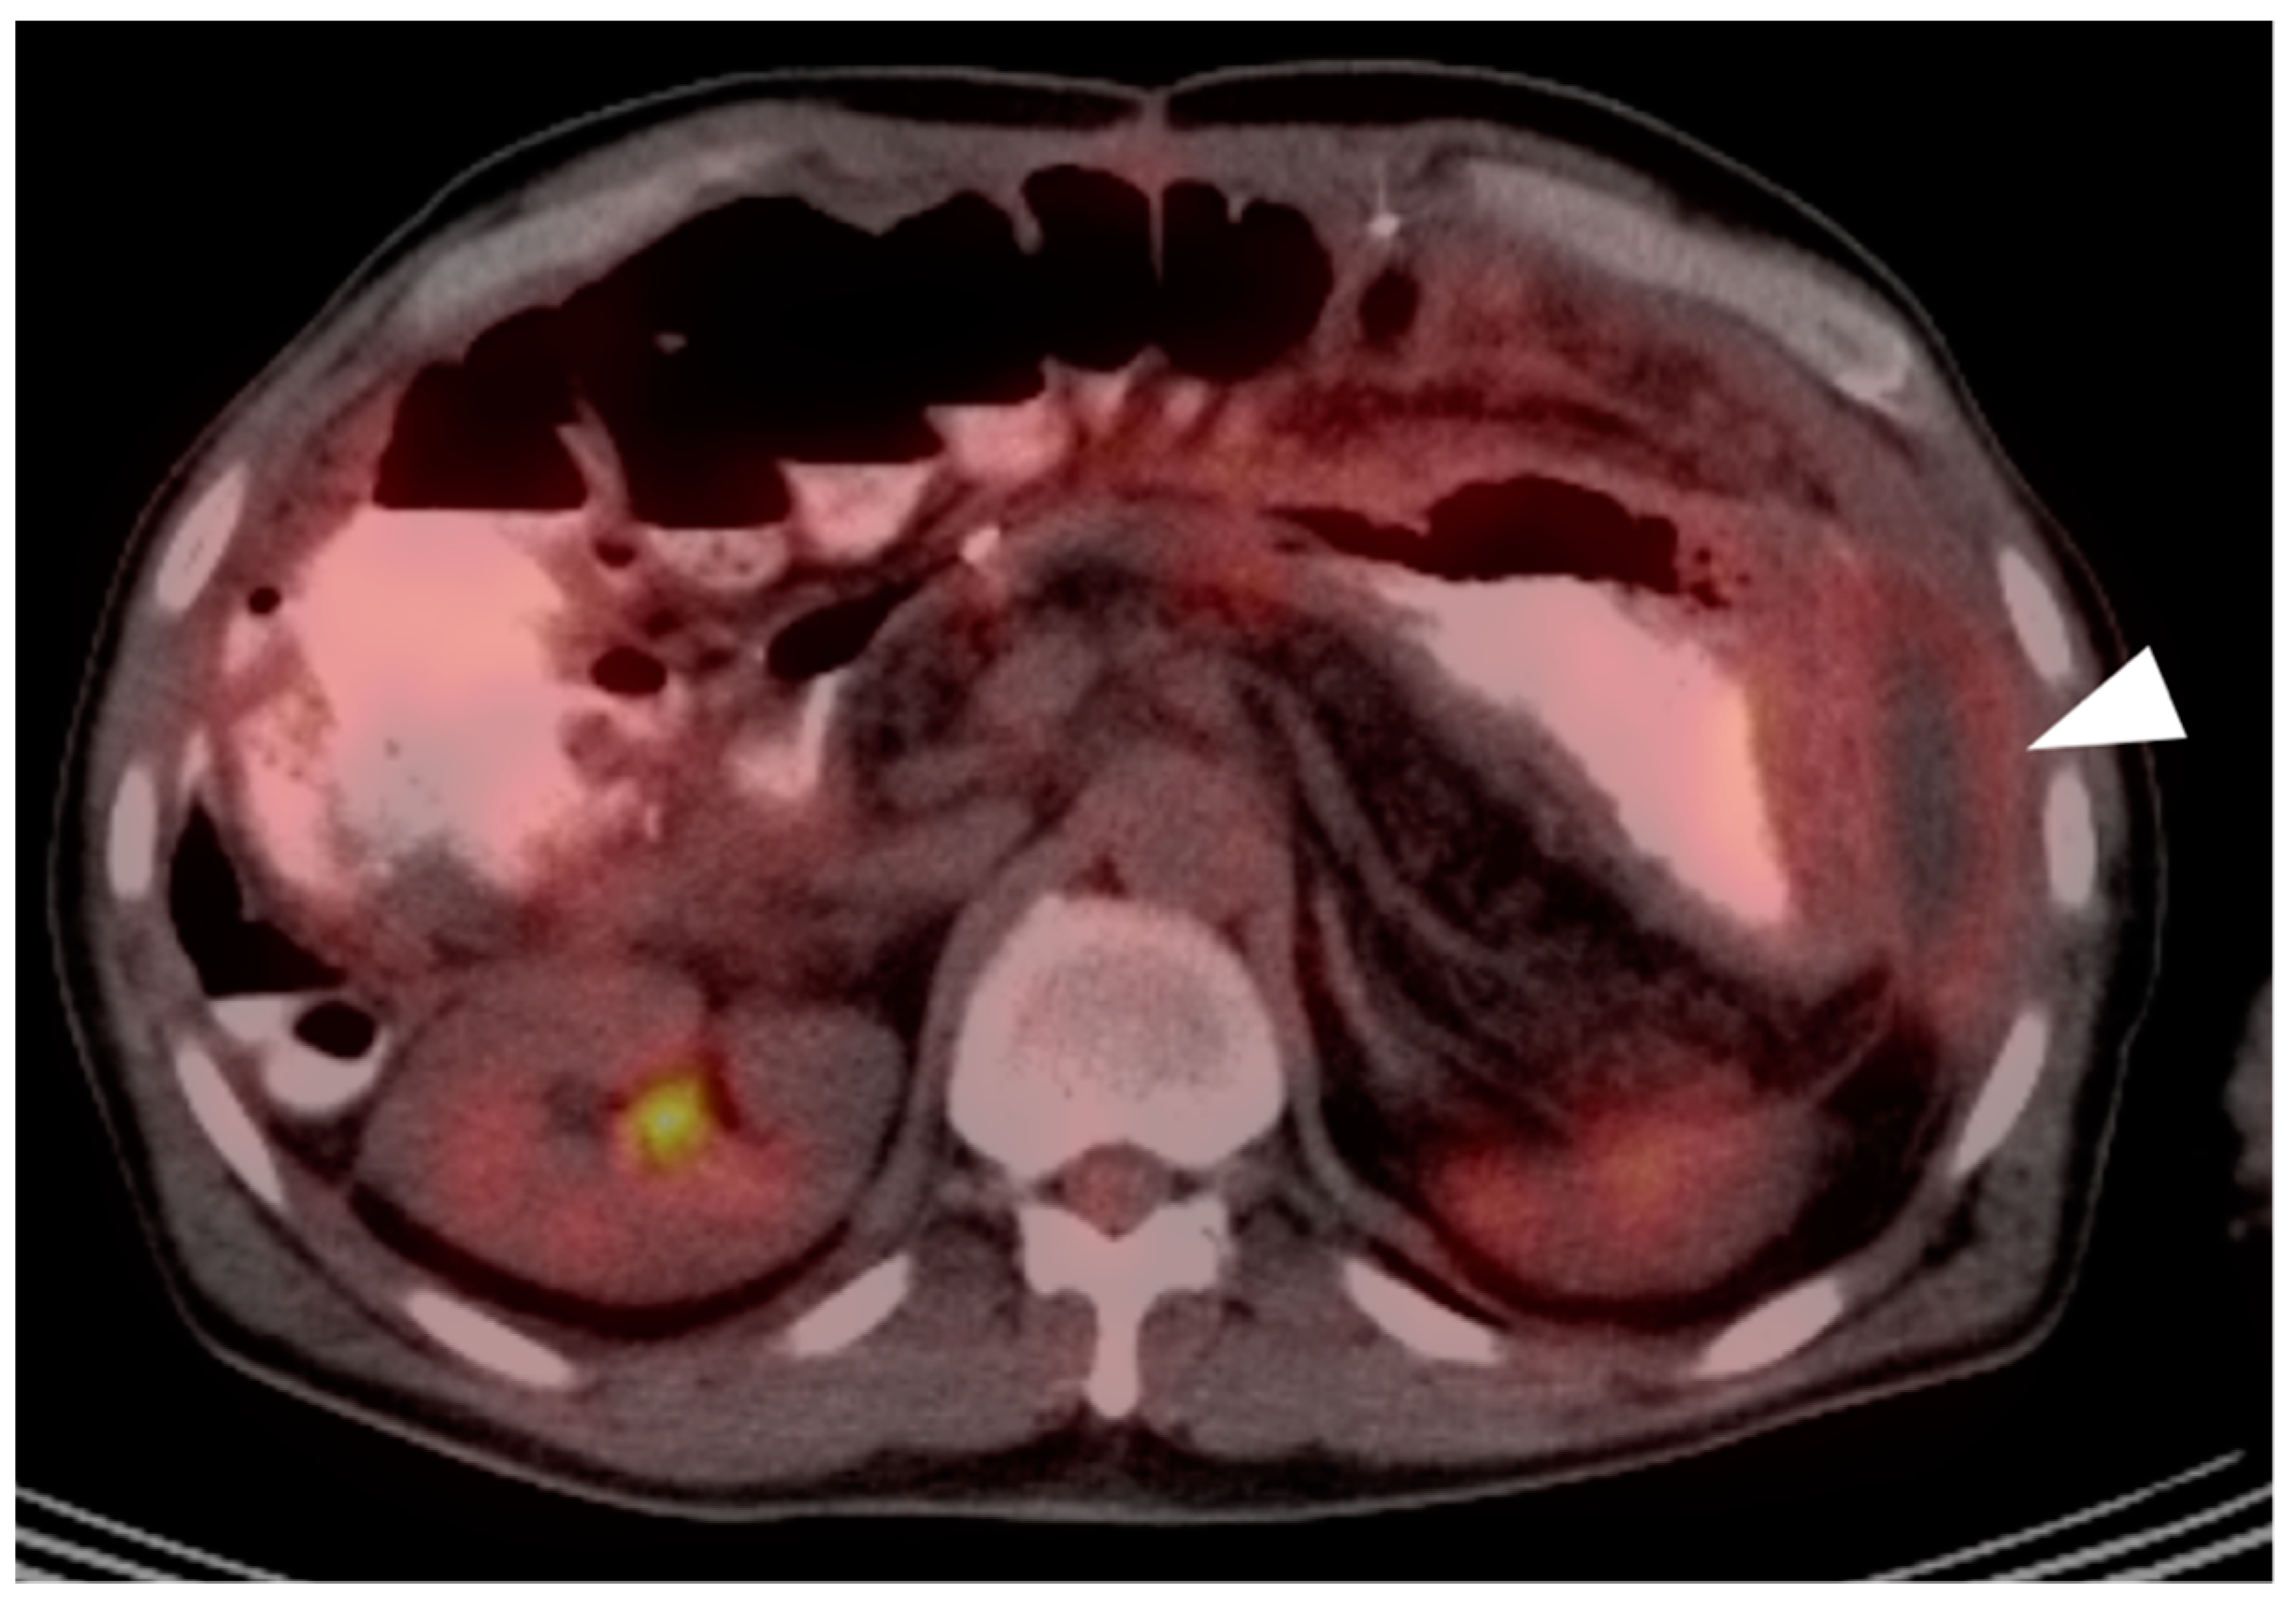

7. Adrenal Cancer